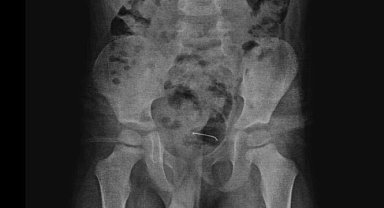

5 yaşındaki çocuğun yuttuğu toplu iğne, ameliyatla çıkarıldı